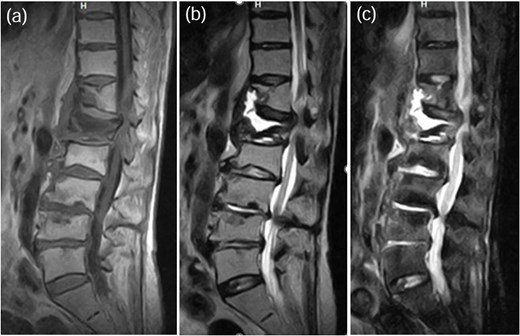

A 75-year-old woman presented with a 1-month history of lower back pain. She had no prior history suggestive of being immunocompromised. No neurological deficits were observed; however, the patient experienced severe back pain, which made it difficult to maintain a seated position. A computed tomography (CT)scan revealed erosion of showed the Th7-Th8 vertebral endplates, with associated diffuse idiopathic skeletal hyperostosis (DISH) (Fig. 1a). Blood tests showed a mild increase in inflammatory markers (C-reactive protein [CRP]: 1.02 mg/dL, white blood cells [WBC]: 6.0 × 103 per μL). Magnetic resonance imaging (MRI) demonstrated signal changes in the Th7-Th8 region (Fig. 2). A biopsy of the Th7-Th8 intervertebral disk confirmed the presence of methicillin-susceptible Staphylococcus aureus (MSSA). She was diagnosed with Th7-Th8 pyogenic spondylitis and initially treated conservatively with antibiotics therapy (cefazolin) and a rigid brace. However, after 4 weeks, her symptoms persisted, and a follow-up CT showed further progression of the destructive changes at the Th7-Th8 endplates (Fig. 1b). Her WBC was 6.4 × 103 per μL, and CRP was 1.19 mg/ dL. Spinal instrumentation surgery was planned, and an assessment of osteoporosis was conducted. The T-scores at the lumbar spine and total hip were −1.4 and −0.9, respectively, and the Hounsfield unit (HU) value at L1 was 79. Posterior PPS fixation was performed from Th5 to Th10 using CAPS at Th5 and Th10, along with the placement of a TMC at Th7-Th8 via a costovertebral approach (Fig. 3). Blood examination results returned to within the normal range at 3 weeks after surgery. Two years after surgery, there was no recurrence of infection and no evidence of screw loosening. The local kyphosis angle was 11° immediately postoperatively and was maintained at 10° at the final follow-up.

MRI demonstrated signal changes at Th7-Th8, with low intensity on T1-weighted images (a), high intensity on T2-weighted images (b), and no suppression on short-tau inversion recovery (STIR) images (c).